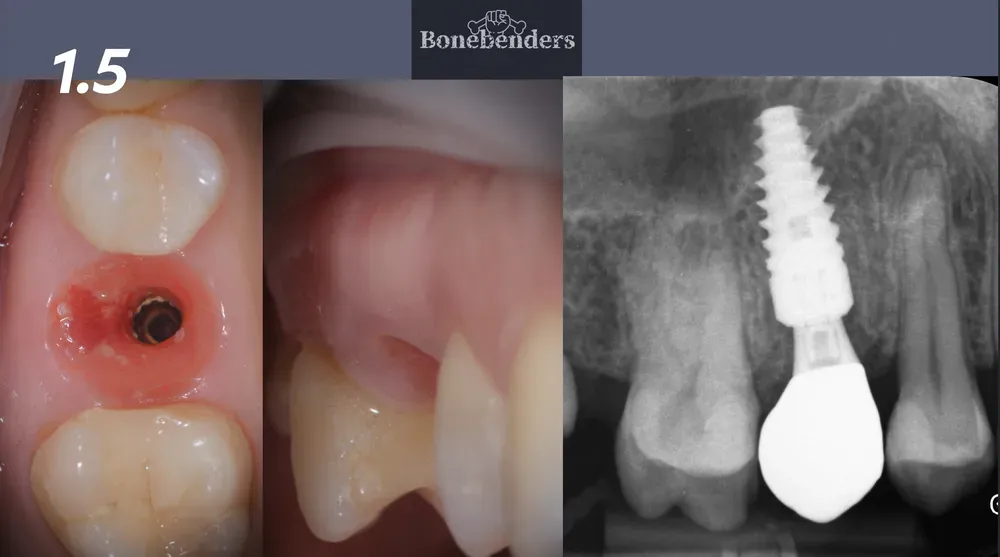

Illustrazione radiografica dell

Illustrazione radiografica dell’asse da correggere in un caso di premolare superiore con frattura radicolare.